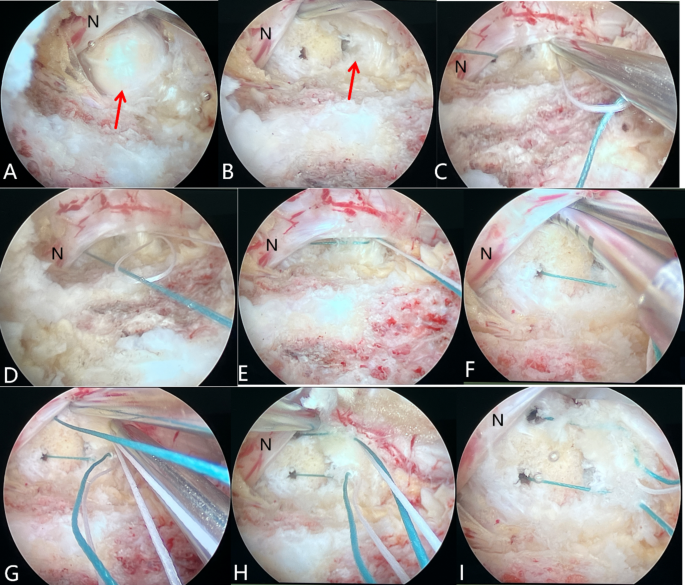

The surgical procedure of the parallel 2-stitch bone-anchoring annulus fibrosus suture technique under arthroscopic-assisted uni-portal spinal surgery. (A) Exposure of the protruding nucleus pulposus (N indicates the traversing nerve root). (B) Excision of the nucleus pulposus reveals the damaged annulus fibrosus and the annulus fibrosus is broken on one side adjacent to the inferior vertebral body. (C) Penetration of the first stitch into the inferior vertebral body. (D,E) Penetration of the second stitch at the lateral section of the annulus fibrosus and tightening with the first stitch to tie a square knot. (F–H) Repeat the above operation to tie another knot. (I) Cutting the two parallel stitches after knotting.